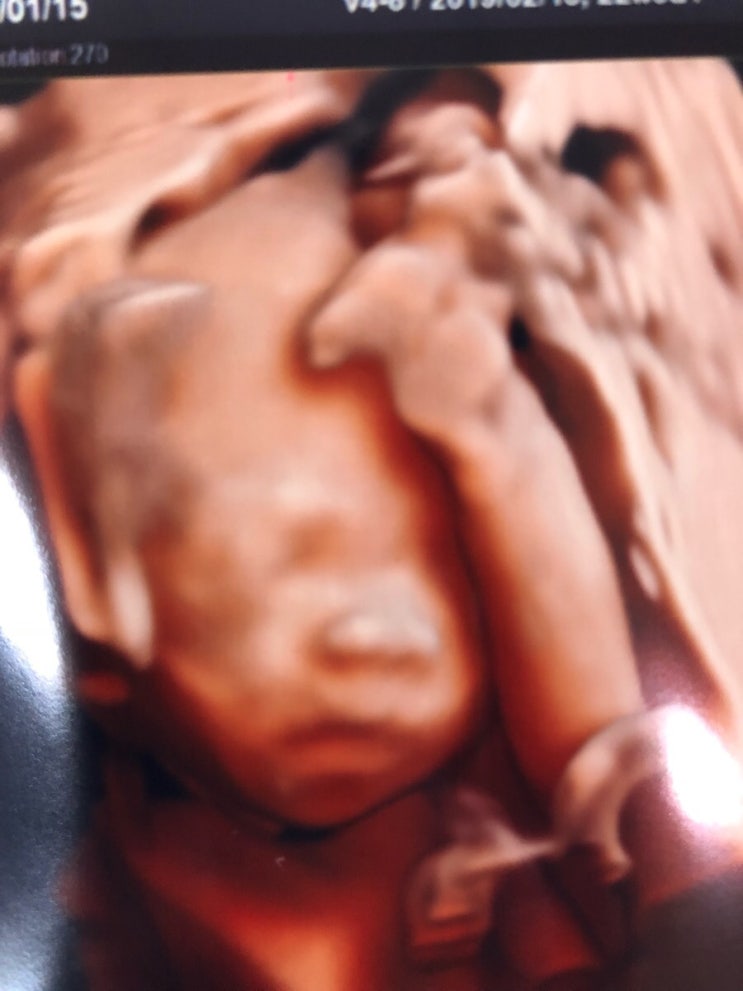

임신22주 정밀초음파/아산병원 제왕절개예약/임신22주 증상 색소침착/배크기/몸무게/폭풍태동

임신22주 정밀초음파 아산병원 제왕절개 예약 임신22주 증상 색소침착, 배크기, 몸무게 임신22주가 되어 아...